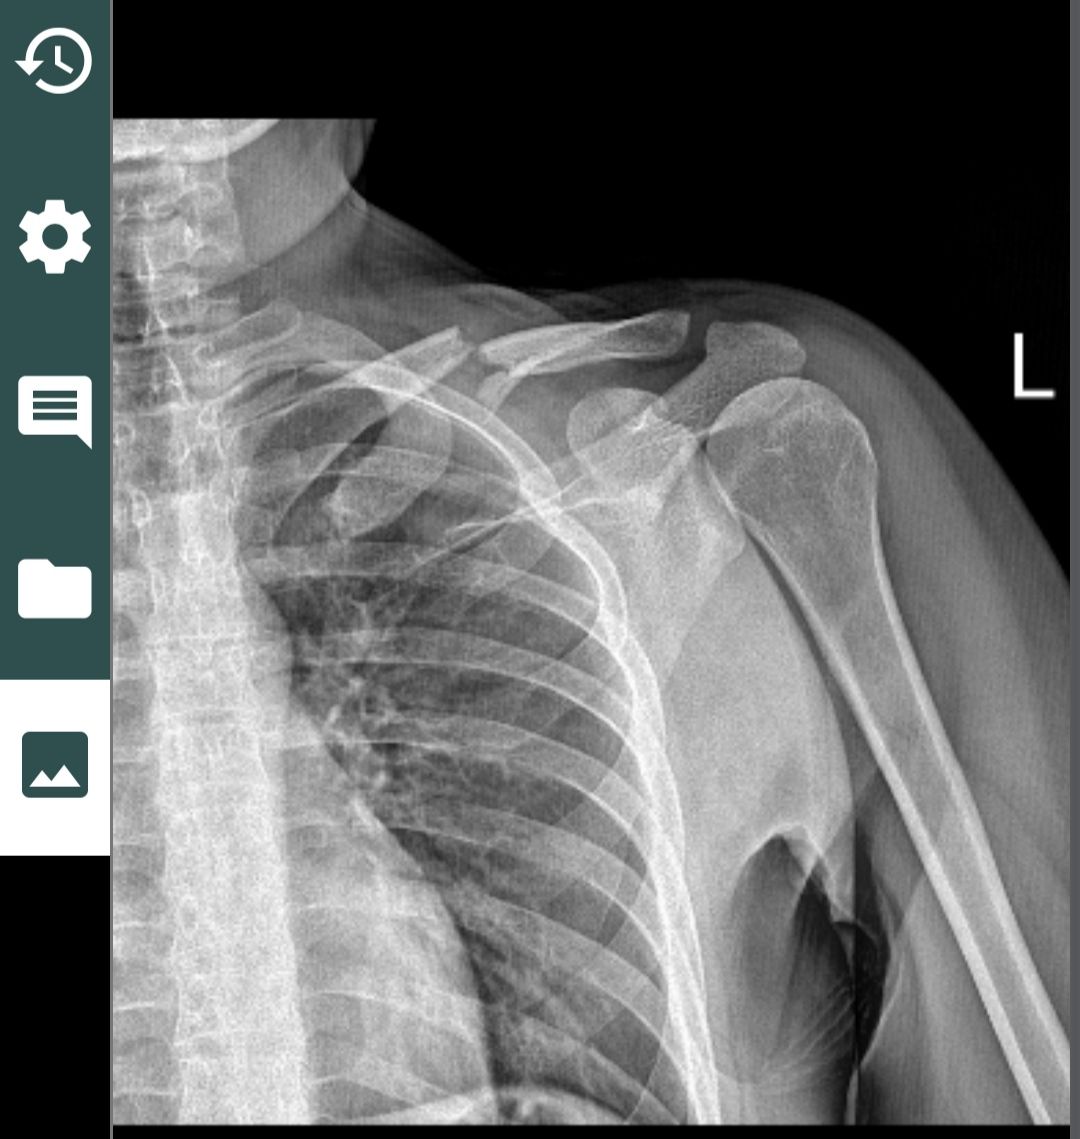

@caglar14 Aynı ameliyatı oldum 3. ay sonunda ip koptu. Çok sinirim bozuldu. Şimdi kemik yukarıda duruyor. Sadece benim mi başıma geliyor derken demek ki olabiliyormuş. Bir prof bana sağlam malzeme kullanmama kaynaklı demişti. Anlattığına göre ton kaldıran ip nasıl kopar mış ? Ya iyi tutturamadılar yada malzeme kötü dedi. Arada bir daha operasyon yaptırsam mı diyorum ama alıştım da. Siz bıraktınız mı öyle.